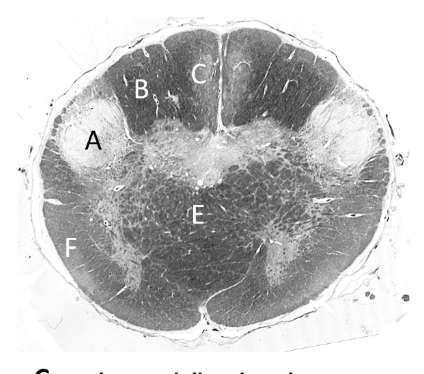

at what level is this?

spino-medullary junction

what is a?

spinal trigeminal nucleus

what is b?

nucleus cuneatus (sm)

what is c?

fasciculus gracilis (sm)

what is e?

pyramidal decussation

what is f?

spinocerebellar & (more medial) spinothalamic tract